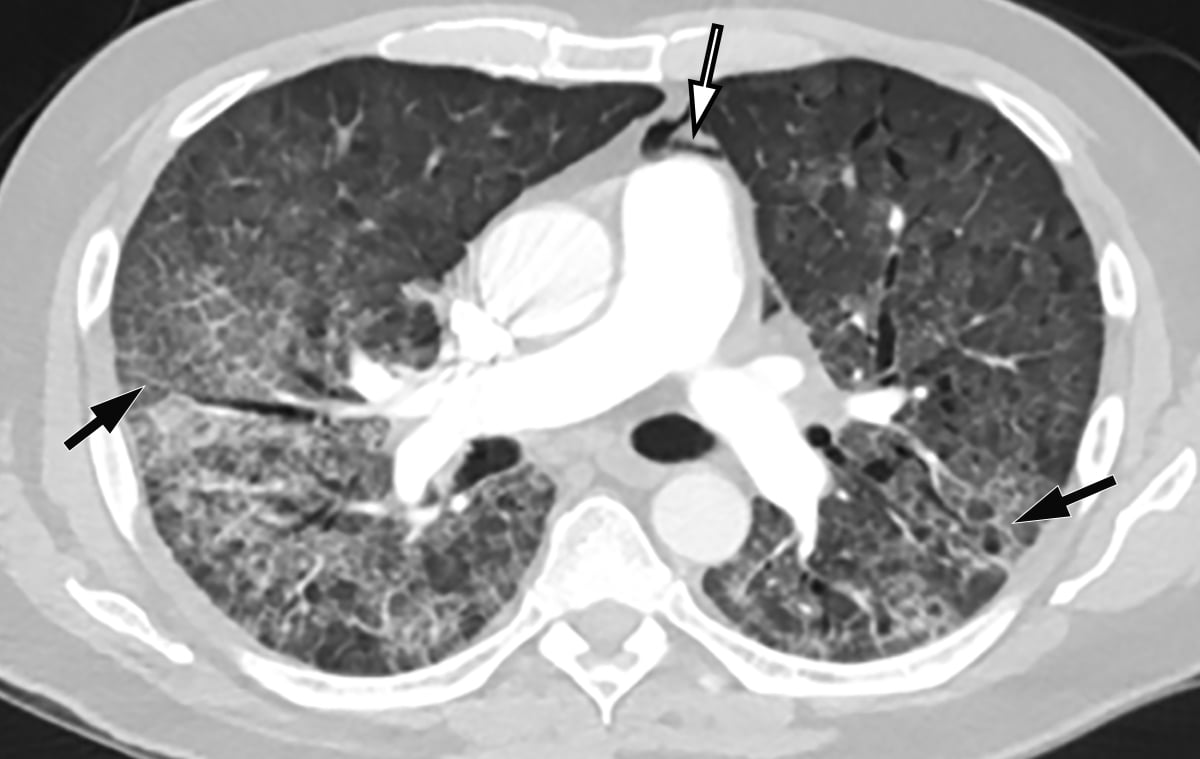

This photo gallery shows the variety of radiological presentations of COVID-19 (SARS-CoV-2) in medical imaging, including computed tomography (CT), radiograph X-rays, ultrasound, echocardiograms and magnetic resonance imaging (MRI). The radiology images show examples of typical COVID pneumonia in the lungs and the numerous complications the virus causes in the body in multiple organs, including the brain, kidneys, heart, abdomen and vascular system.